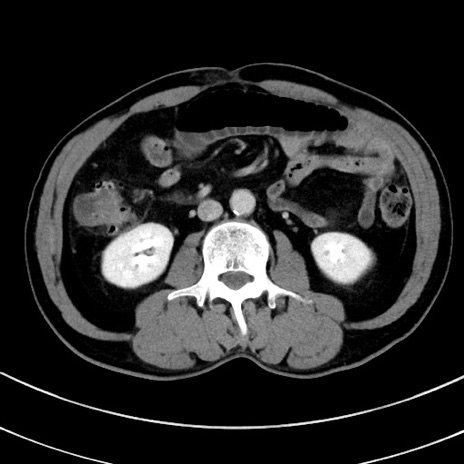

冠状断像

【症例】 60歳代男性

【主訴】 黒色吐物

【現病歴】 4日前から嘔気自覚、2日前の朝食後にも嘔気あり、自分で手で嘔吐反射起こし嘔吐したところ血が混ざっていたため受診。

【既往歴】 5年前汎発性腹膜炎を伴う急性虫垂炎で手術、高血圧、前立腺肥大症、高脂血症

【身体所見】 腹部正中に手術癩痕あり 腹部平坦・軟圧痛なし膨満感あり

【データ】WBC 8400、CRP 4.54